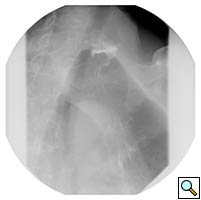

A 67 year old patient with a history of transhiatal esophagectomy (THE) and sub-sternal gastric pull-up ten years prior, at another institution, for early stage esophageal cancer presented with progressive dysphagia to solids. An initial esophagogastroduodenoscopy (EGD) found a large retained food bolus as well as tortuosity and dilatation of the cervical esophagus proximal to the esophagogastric anastomosis. No evidence of intrinsic anastomotic stricture or fibrosis was noted, but there was extrinsic compression. A barium esophagogram revealed significant extrinsic compression of the upper esophagus in the area of the anastomosis at the left clavicular head, with associated narrowing of the lumen and minimal transit of oral contrast (Figure 1). A computed tomography scan of the neck confirmed the sub-sternal location of the gastric pull-up within the anterior mediastinum, and revealed dilatation of the esophagus proximal to the anastomosis, with no associated masses or disease recurrence (Figure 2). The left sternoclavicular joint (SCJ) appeared to be compressing the conduit and was the point of obstruction.